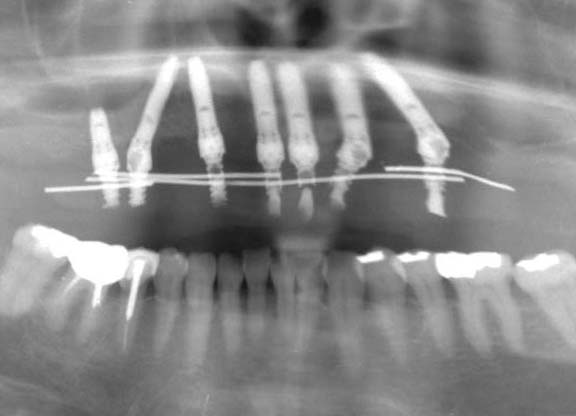

術前のレントゲン写真

術直後(手術当日)のレントゲン写真(右)

術前のレントゲン写真(左)と術直後(手術当日)のレントゲン写真(右)